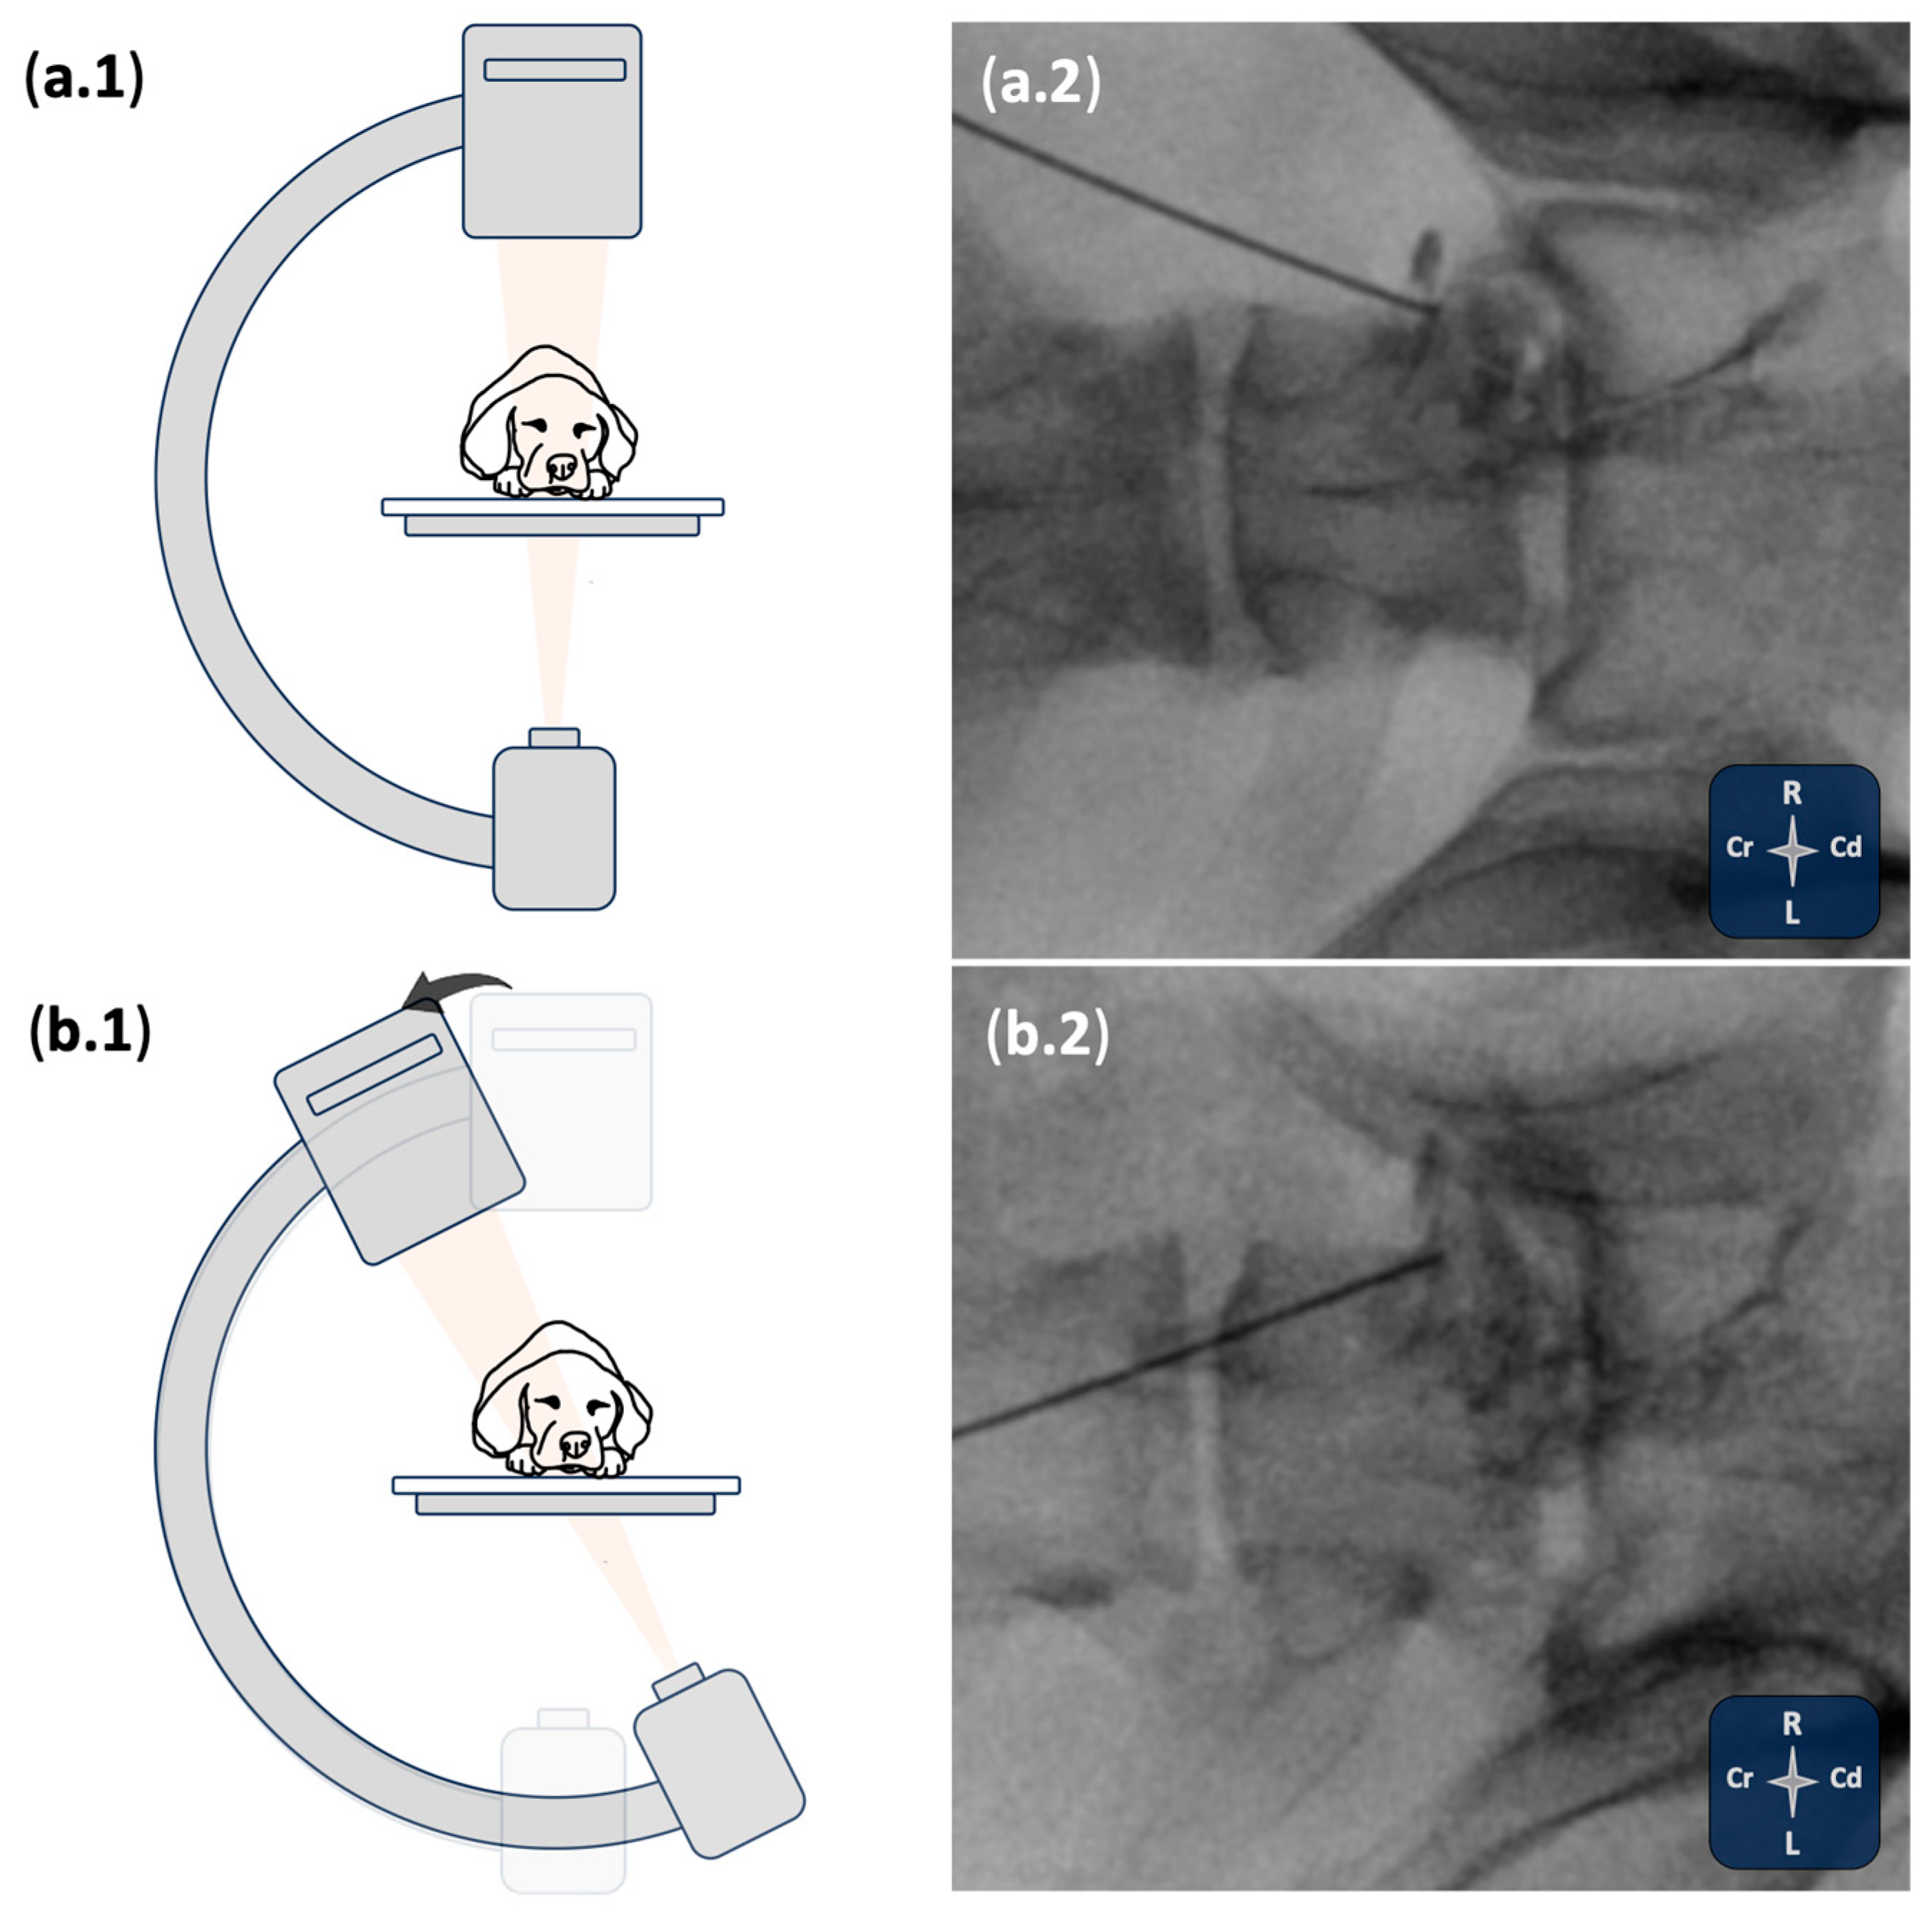

2.1. Phase I: Ultrasound- and Fluoroscopy-Guided Technique

3.1. Phase I: Ultrasound- and Fluoroscopy-Guided Technique